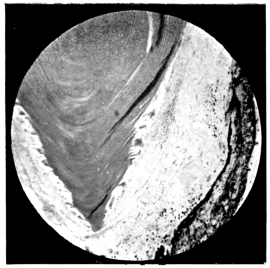

PLATE II.

FACING

PAGE

10.

LENS DISLOCATED BETWEEN CILIARY BODY AND SCLERA

curly bracket span

38

11.

NUCLEUS OF CATARACT FREELY MOVABLE BETWEEN THE AQUEOUS AND VITREOUS CHAMBERS

12.

LENS IMPACTED IN ANGLE OF ANTERIOR CHAMBER

13.

CAPSULE OF MORGAGNIAN CATARACT IMPACTED IN ANGLE OF ANTERIOR CHAMBER

14.

LENS FLOATING FREE IN VITREOUS CHAMBER

15.

LENS LIGHTLY IMPRISONED IN EXUDATE INTO VITREOUS CAVITY